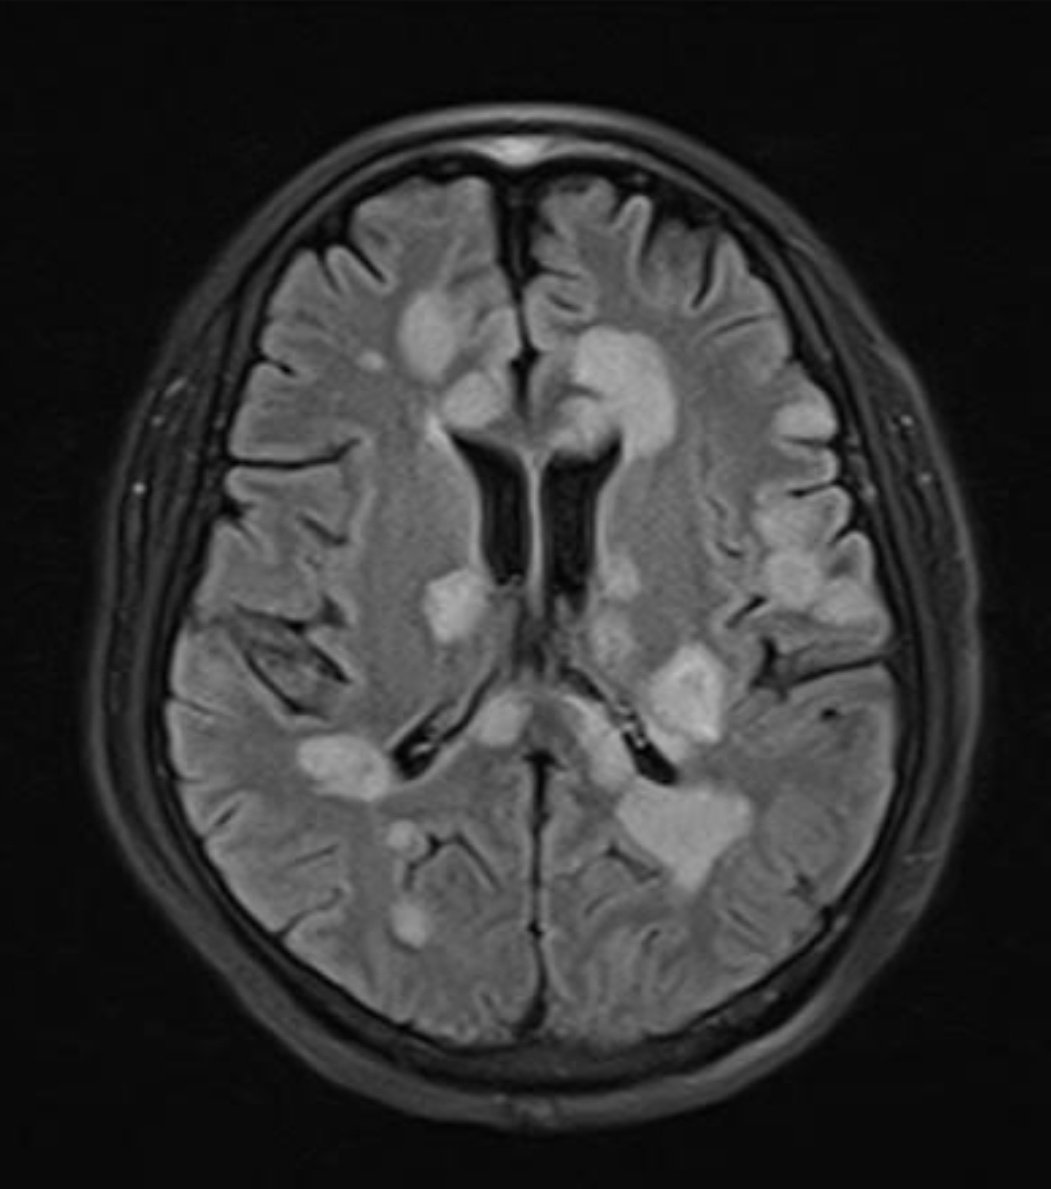

From the July-September 2025 Issue of #Neurographics: Recurrent Stroke-Like Episodes in X-Linked Charcot-Marie-Tooth Type 1 Disease: Characteristic Brain MRI Findings ow.ly/W9vt50WITmU